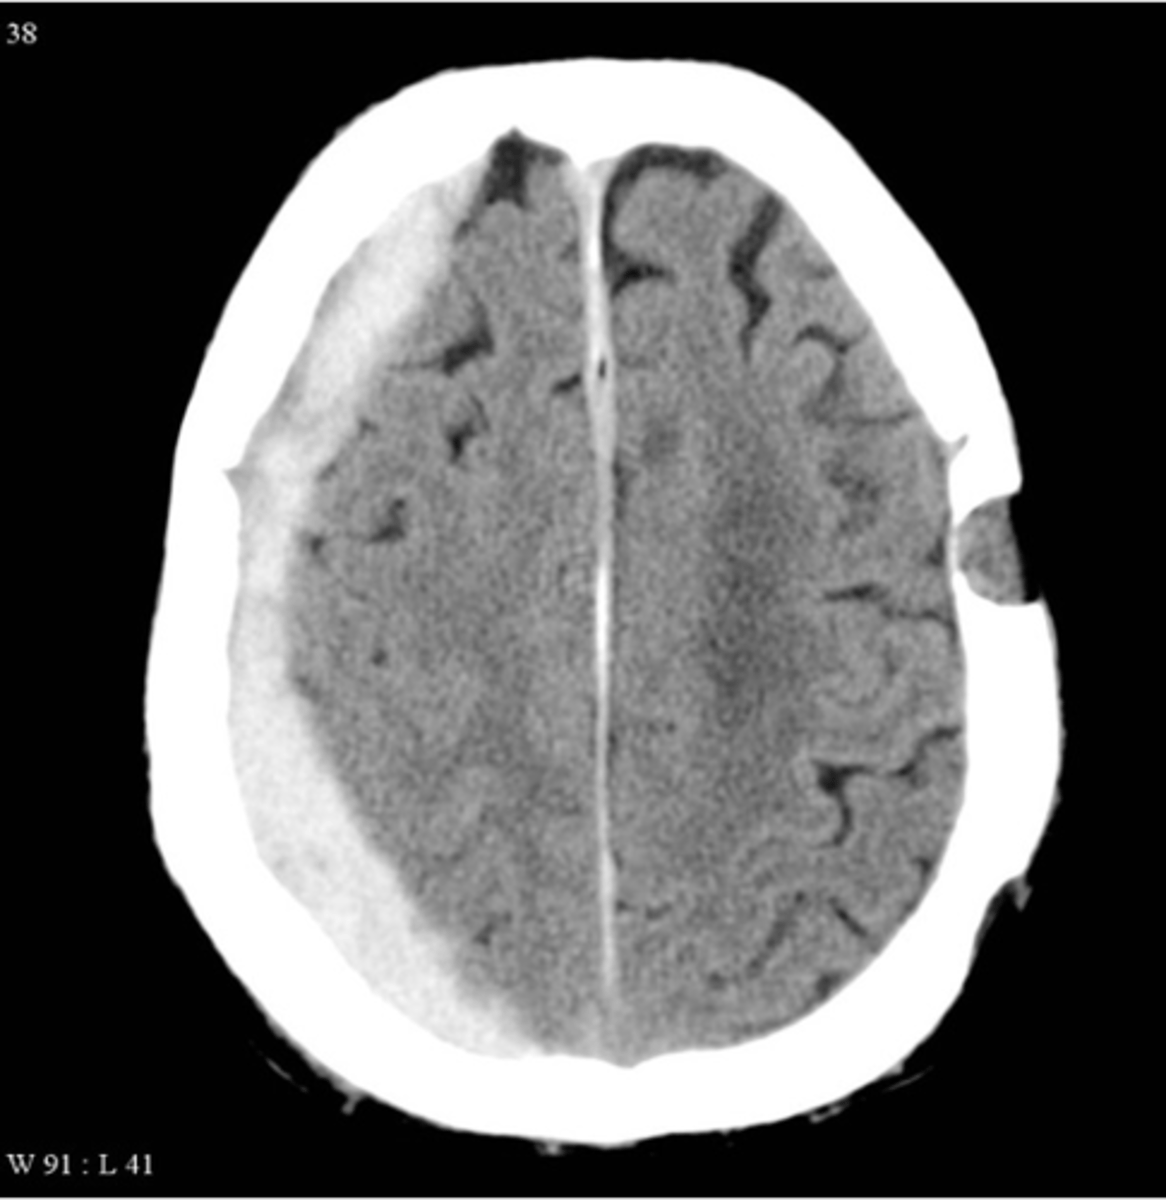

subdural hematoma

Crescent-shaped intracranial bleeding after head injury in the elderly; can be acute on chronic

Dark (on CT) means

old blood

White means

new blood or CSF

Can you have a subdural hematoma that is acute on chronic?

yes